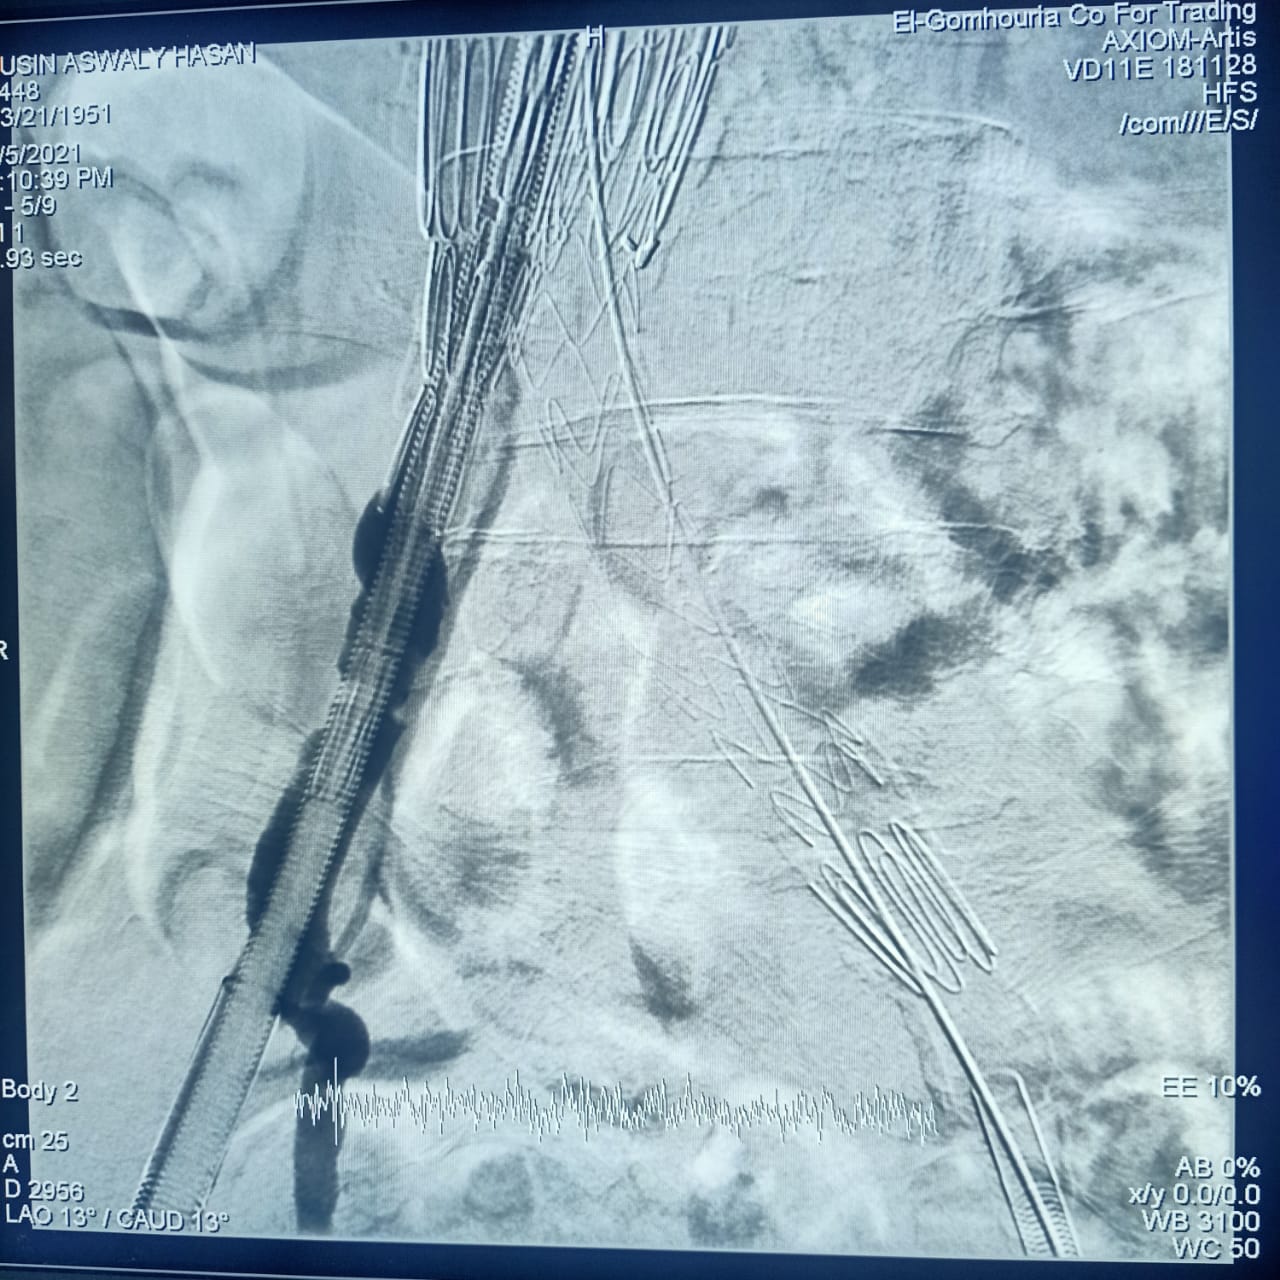

وأشارت هيئة الرعاية الصحية، أن CERAB، EVAR هي من أحدث التقنيات العلاجية لأمراض تمدد وانسداد الشريان الأورطي البطني والحرقفي (بدون جراحة)، من خلال علاج تمدد الشريان الأورطي البطني عن طريق القسطرة باستخدام تقنية الدعامات المغطاة EVAR، وكذلك علاج انسداد الشريان الأورطي البطني والحرقفي عن طريق القسطرة باستخدام تقنية الدعامات المغطاة ذات المقاومة العالية للانسداد CERAB، وذلك وفقًا لأحدث ممارسات الصحة العالمية.

وتابعت الهيئة: أن العملية الأولى كانت لعلاج مُسِّن يبلغ من العمر 70 عامًا يعاني من تمدد بالشريان الأورطي البطني وتم علاجه باستخدام تقنية الدعامات المغطاة EVAR، بينما كانت العملية الثانية لعلاج مريض يبلغ من العمر 65 عامًا باستخدام تقنية الدعامات المغطاة المقاومة للانسداد CERAB، مشيرة إلى استقرار الحالة الصحية للمريضين وإجراء العمليات بنجاح على يد أمهر الأطقم الطبية والتمريضية في مستشفى طيبة التخصصي بالأقصر.